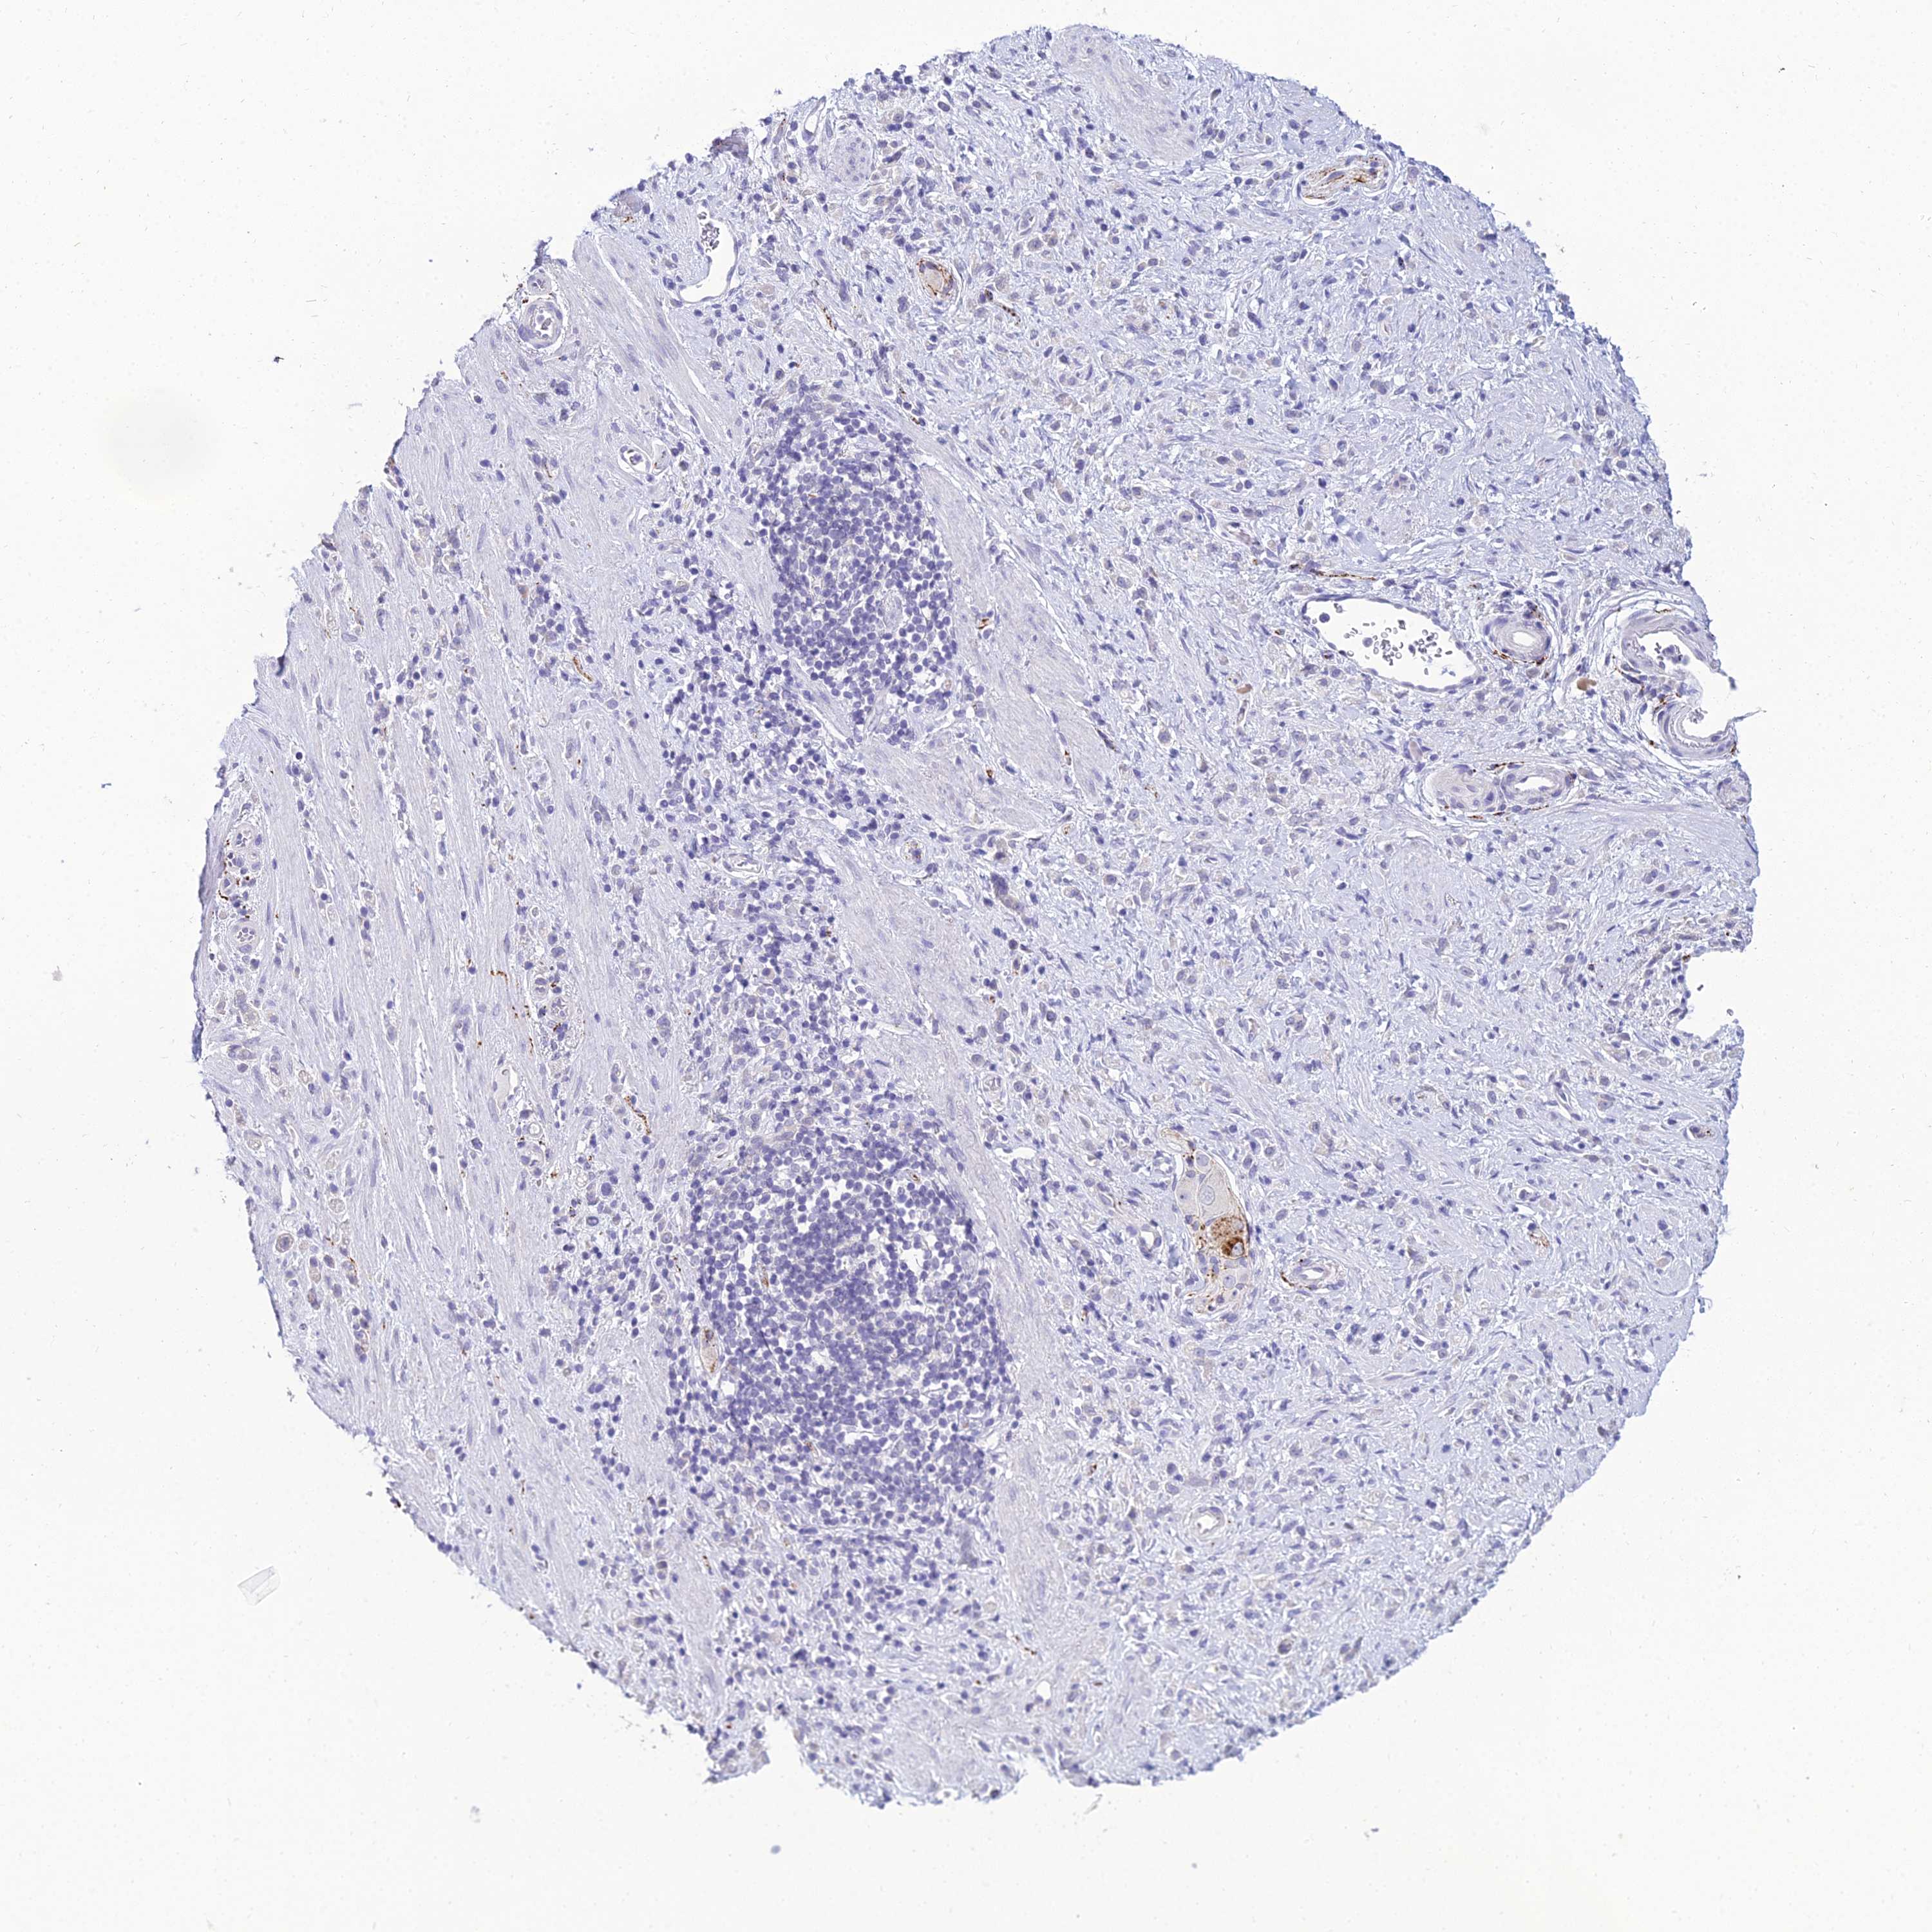

STOMACH CANCER - Protein expressioni

A mouse-over function shows sample information and annotation data. Click on an image to view it in a full screen mode. Samples can be filtered based on level of antibody staining by selecting one or several of the following categories: high, medium, low and not detected. The assay and annotation is described here.

Note that samples used for immunohistochemistry by the Human Protein Atlas do not correspond to samples in the TCGA dataset.

Antibody stainingi

Antibody staining in the annotated cell types in the current human tissue is reported as not detected, low, medium, or high, based on conventional immunohistochemistry profiling in selected tissues. This score is based on the combination of the staining intensity and fraction of stained cells.

Each image is clickable and will lead to virtual microscopy that enables deeper exploration of all samples and also displays staining intensity scores, fraction scores and subcellular localization as well as patient and tissue information for each sample.

Antibody HPA056798

Staining

High

Medium

Low

Not detected

Intensity

Strong

Moderate

Weak

Negative

Quantity

>75%

75%-25%

<25%

None

Location

Nuclear

Cytoplasmic/membranous

Cytoplasmic/membranous,nuclear

Adenocarcinoma, NOS